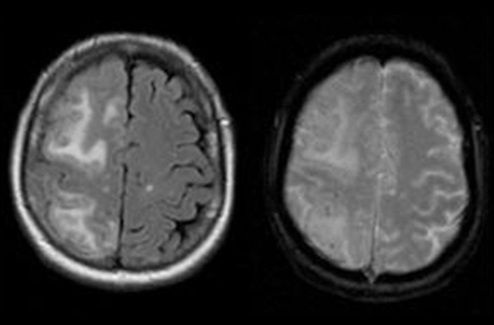

- Análisis de sangre basado en IA detecta múltiples trastornos cerebrales a partir de una sola muestra

- Un ensayo automatizado de NfL respalda el seguimiento de trastornos neurológicos